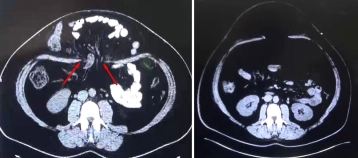

Bei der jungen Patientin hatte sich postpartal – ohne vorangegangenen abdominellen Eingriff – eine monströse Bauchdeckenhernie entwickelt, die zu einer Verlagerung großer Darmanteile in den Bruchsack führte (linkes CT-Bild mit der markierten Bruchpforte).

Bei fortgeschrittener Eventration der Eingeweide durch den Fasziendefekt hatte man sich präoperativ zu einer Konditionierung der Bauchdecken mit einem progressiven Pneumoperitoneum entschlossen. Durch diese Maßnahme kam es zu einer vollständigen spontanen Reposition des Bruchsackinhaltes.